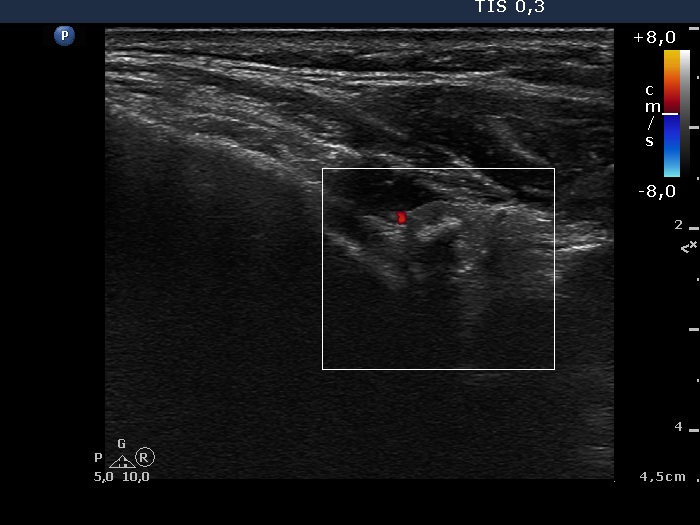

Ultrasonography: a large lesion composed of multiple moderately hypoechogenic and hyperechogenic nodules occupies almost the entire right lobe. There was a small hypoechogenic nodule in the upper pole while a cystic nodule in the central part of the left lobe. The former presented coarse and microcalcifications, too. The vascularization was not specific.